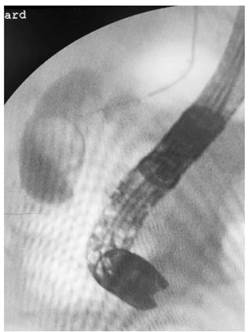

Por lo anterior, se decide realizar abordaje endoscópico por CPRE, el cual muestra papila intradiverticular alargada hasta la segunda porción del duodeno. Se intenta canular con guía y papilotomo hasta los conductos hepáticos; luego de 3 intentos e infundibulotomía con Needleknife, no es posible el ingreso a la vía biliar, por lo que se considera fallida. En un segundo intento de CPRE a los 5 días después del primer procedimiento se logra canalizar con guía metálica hasta los hepáticos; mediante papilotomía amplia sobre guía metálica se logra extracción de cálculo ovoide y grande del colédoco (Figura 1). Su evolución posprocedimiento fue satisfactoria hasta las 8 horas, cuando presenta súbitamente dolor abdominal, localizado en el hipocondrio derecho, de alta intensidad, sin signos de irritación peritoneal.

Figura 1 Fluoroscopia intraoperatoria-colangiopancreatografía retró-grada endoscópica, acceso a la vía biliar.